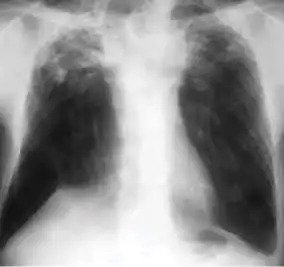

2. Any cavitary lesion - Lucency (darkened area) within the lung parenchyma, with or without irregular margins that might be surrounded by an area of airspace consolidation or infiltrates, or by nodular or fibrotic (reticular) densities, or both. The walls surrounding the lucent area can be thick or thin. Calcification can exist around a cavity.

Chest X-ray of a person with advanced tuberculosis: Infection in both lungs is marked by white arrow-heads, and the formation of a cavity is marked by black arrows.